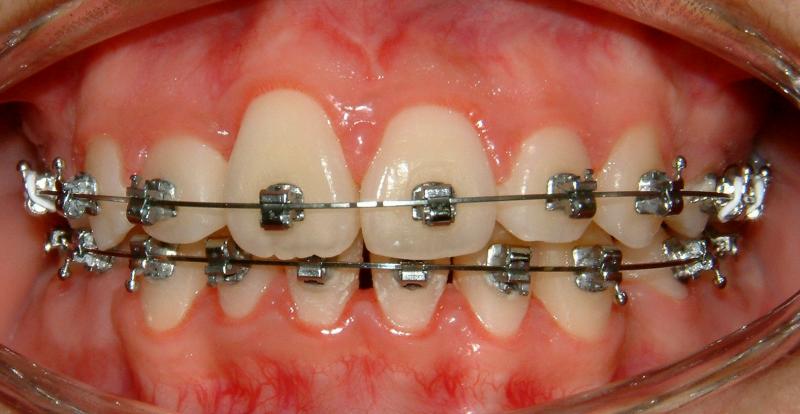

The upper right central incisor and lateral incisor form 2 rows. It would be a fatal mistake to extract either one of these two. It might be the case if the patient has no access to the correct orthodontic treatment. In this case, the 1st premolars are removed. Initial and some progress data are presented in Figs. 1-5.

Fig. 1 Upper right central and lateral incisors, forming double rows -- front view